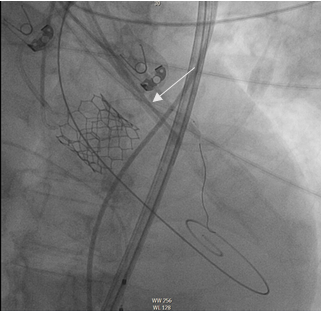

Percutaneous therapeutic access through the right femoral artery, successful implantation of Sapien 3 valve, nº26 (Edwards) (Figure 7 and 8).

Figure 8 Implantation of aortic prosthesis.

The patient was able to go from an initial gradient of 64 mmHg to 0 mmHg, without regurgitation. The hemodynamic improvement was evident from the first moment (Figure 9 and 10).